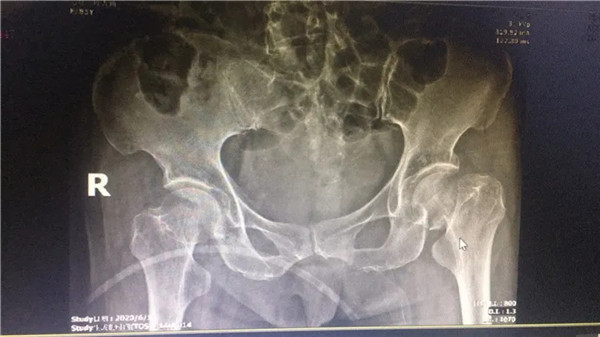

術(shù)前

經(jīng)拍片顯示,陳阿婆左側(cè)股骨頸骨折,須入院手術(shù)治療。一聽要手術(shù),家人便不禁擔(dān)憂起來,這么大年紀(jì)動(dòng)手術(shù),身體吃得消嗎?危立軍副院長解釋道:高齡病人股骨頸骨折臥床,會(huì)導(dǎo)致一系列嚴(yán)重的并發(fā)癥,如疼痛,肺炎、血栓、泌尿系感染等等。隨便哪一項(xiàng)發(fā)生,對(duì)病人都是致命打擊,如果病人身體情況不是很差,還是建議進(jìn)行手術(shù),人工關(guān)節(jié)置換,能讓病人盡早恢復(fù)患肢活動(dòng),縮短臥床時(shí)間,降低死亡率及其他并發(fā)癥的發(fā)生幾率。在聽了危副院長的介紹后,家人遂即辦理了住院手續(xù)。